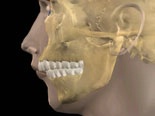

Dentala anomalier

tänder som sitter snett Dentala_anomalier_efter

Före behandling Efter behandling

Med dental anomali menas att enskilda tänder är tippade eller roterade. Tänder som inte kommit fram, trots att anlaget finns, är också vanligt förekommande.